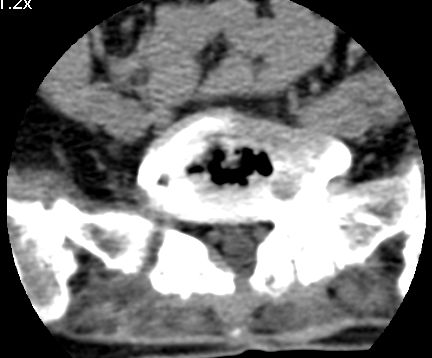

以下是引用余辉在2007-9-4 21:00:00的发言:[br]椎体棘突有点异常(像是被切割了),不知有否手术史,如椎体融合术等。单纯的退行性变可以出现椎间隙变窄,但同时一般会出现椎体上下缘的硬化增生,且椎体间完全融合的机率更小,本例椎体完全融合且椎体上下皮质缘破坏掉了,如果没有手术史,就应该考虑椎间盘炎性病变了,且椎体棘突及棘间韧带的变化也并不是不支持这个,多数小关节也融合了,且其形态也容易让人联想到如强脊炎及类风关等病变。[br][br][本贴已被 余辉 于 2007-9-4 21:03:55 修改过]

以下是引用chry3在2007-9-4 20:42:00的发言:[br]椎间盘病史?是什么样的病史,无双下肢放射痛,那就不是椎间盘突出了。是感染、什么性质的?[br]从图象看椎间隙消失,椎间盘组织未见,锥体滑脱是因为椎间盘溶解造成的[br]l4、5椎体骨质结构未见异常,l5上缘是l4的长期压迫所致[br]还是考虑椎间盘感染,结核。[br]